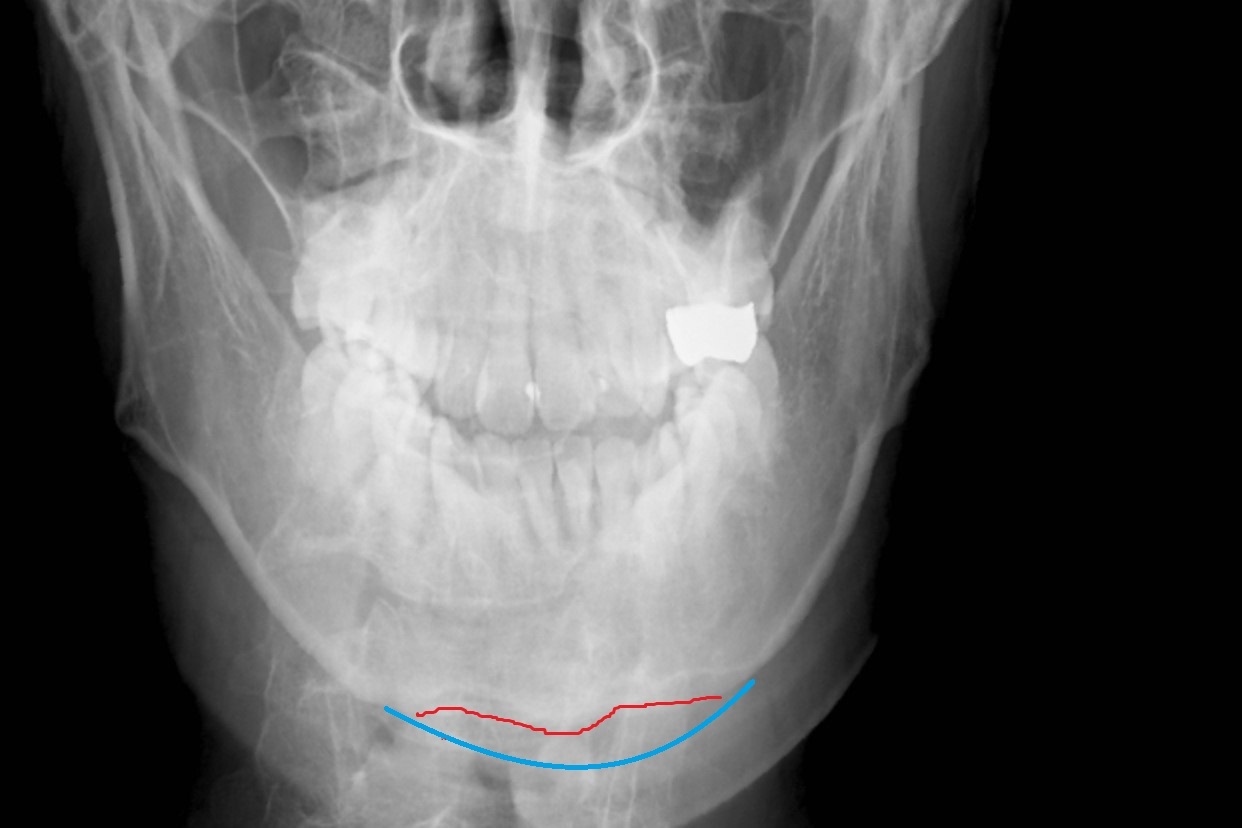

レントゲン写真上も 顎先を水平に削っていますが、側面像では、V型の骨の出っ張りが残っています。